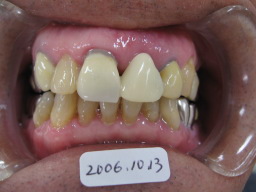

| インプラントして1週間後の状態です。 歯ぐきの傷はほとんど治っています。 仮歯(テック)の状態で、半年程待ちます。 |